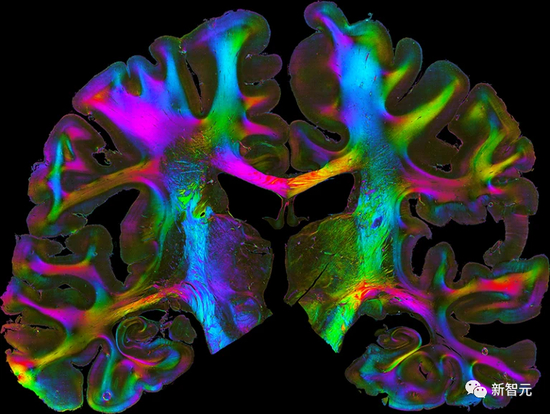

通过创建和组合大约200个大脑皮层和更深脑结构的3D地图,HBP科学家制作了人脑图谱——描绘出大脑的多层次组织,从细胞和分子结构到功能模块和连接性。

在3月份举行的2023年HBP峰会上,Amunts表示:「人脑图谱有点像谷歌地图,不过是大脑的谷歌地图。」

该图谱利用死后的大脑数据生成标准化地图,并且考虑到了人与人之间的自然差异。

利用这个图谱,HBP科学家在前额叶皮层中发现了六个以前未知的脑区域,这些区域有助于记忆、语言、注意力和音乐处理。

同时,将图谱与艾伦人类大脑图谱(Allen Human Brain Atlas)中的基因表达数据相链接后,可用于表征整个大脑的神经元。

利用这些配对的图谱,研究人员揭示了与抑郁症相关的基因表达变化,是如何与额叶皮层的结构和功能变化相联系的。